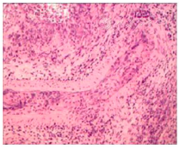

鼻腔黏膜活检提示黏膜重度慢性炎,多量中性粒细胞渗出伴脓肿形成,大面积坏死,并可见不规则肉芽肿形成,坏死组织内可见血管壁炎症细胞浸润,抗酸染色未见阳性杆菌,PAS及PASM特殊染色未见霉菌,免疫组化结果:CD20(部分+),CD3(部分+),CD56(个别+),GRAMB(个别+),Ki-67(+),MP0(+),Perforin(+),TIA-1(部分+),目前暂不甚支持结核、真菌感染及淋巴瘤,比较符合血管炎导致的组织大面积坏死(图4)。

患者血清PR3-ANCA滴度明显升高,肺部CT提示双肺多发结节,鼻腔病理学检查提示中性粒细胞浸润,血管炎所致大面积坏死及不规则肉芽肿形成,故考虑肉芽肿性多血管炎诊断。